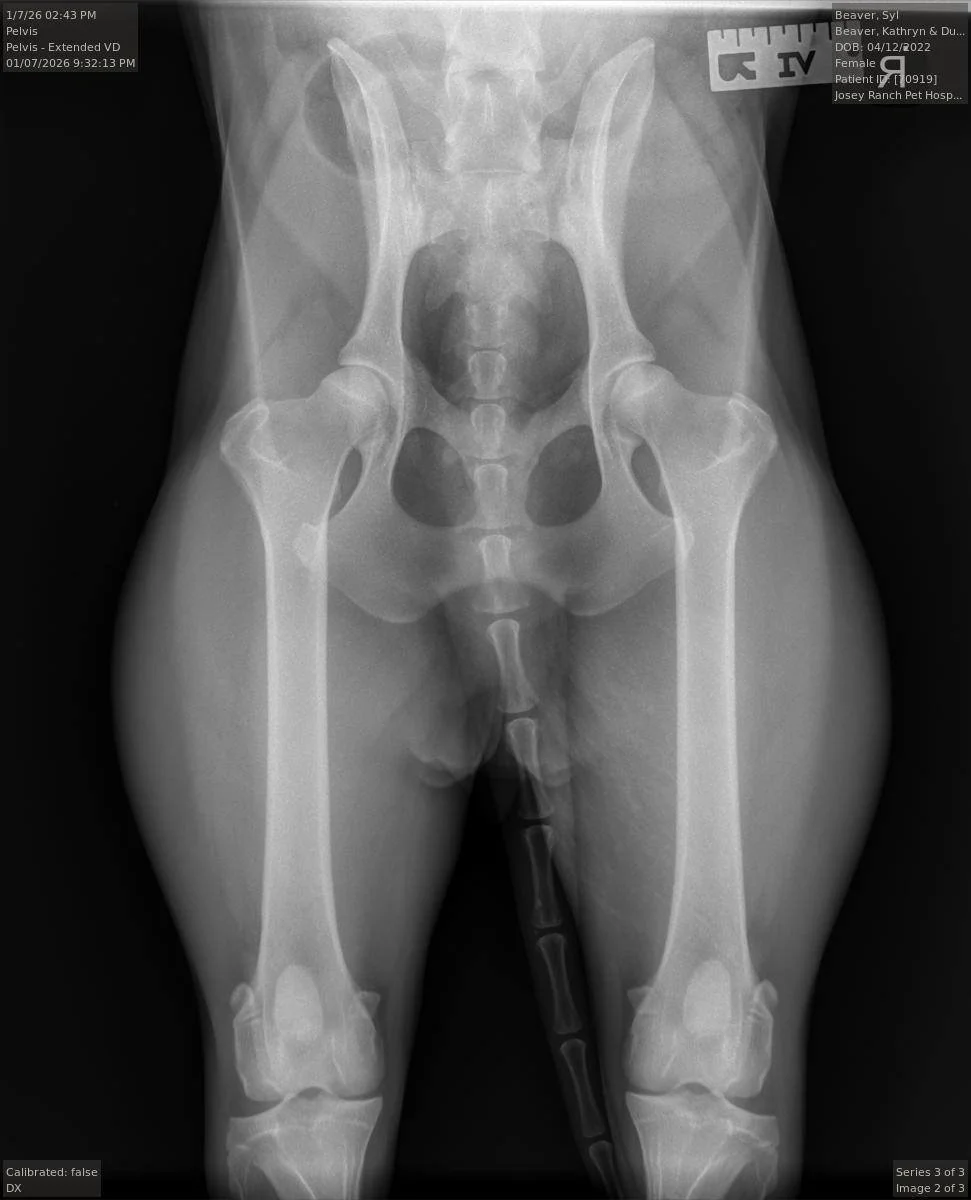

Syl’s hips x-ray, taken at 2 years and 9 months old, intact.

Syl’s OFA Certificate: Hips Excellent